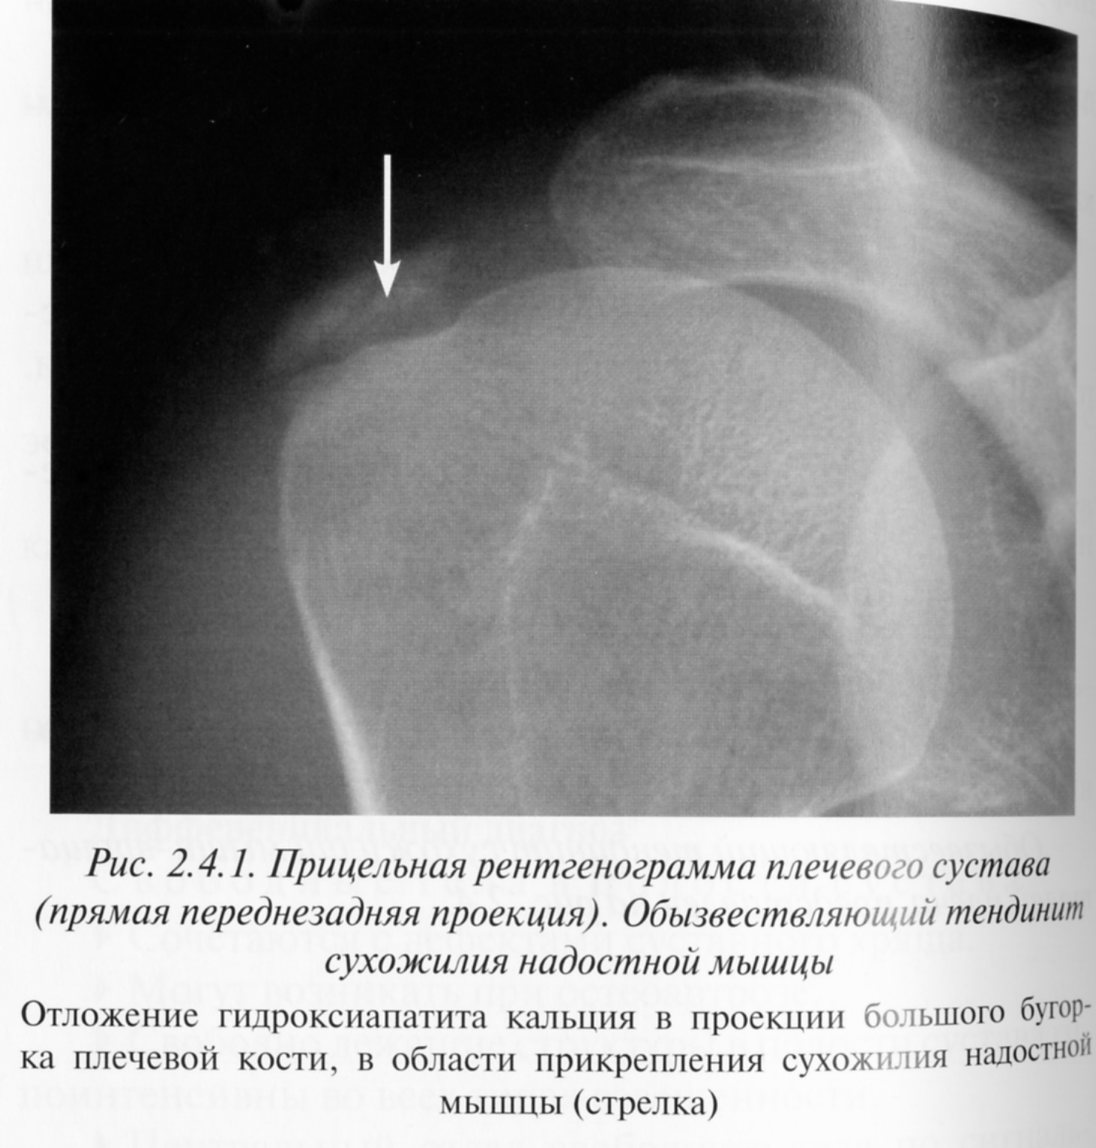

Рентгеновские снимки саркомы плечевого сустава